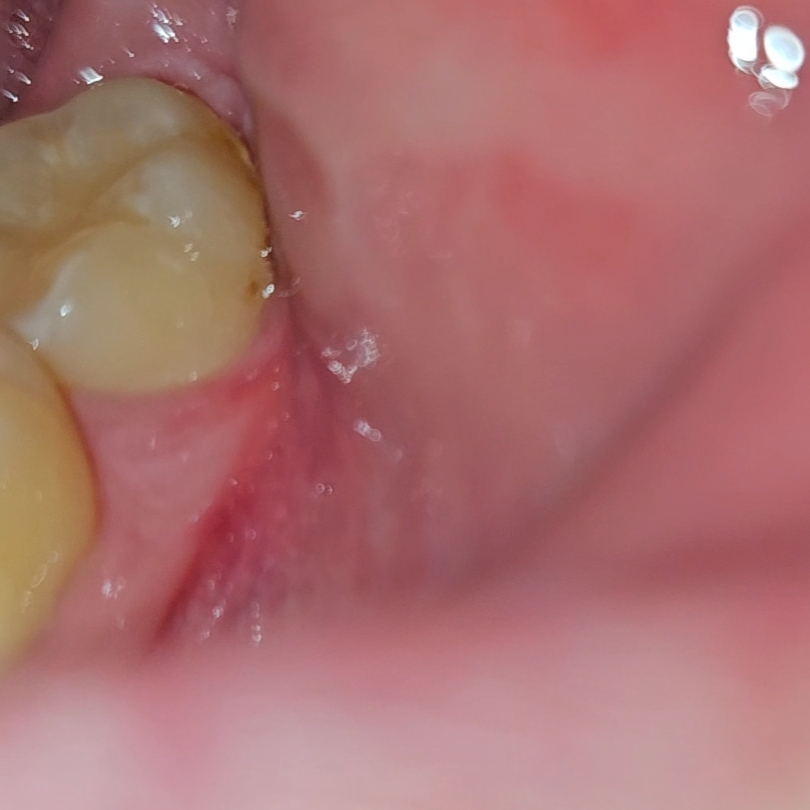

현재 사진상으로 충치의 가능성이 있어 보입니다. 깊은 충치가 아닌 경우에는 긁어내고 레진으로 간단히 치료가 가능하나우선은 진료를 받아보아야 정확한 상태 확인이 가능합니다.

사진에 보이는건 충치는 아니고 치아가 변색된거 같으니 일단 치과에 가셔서 스켈링을 먼저 받아보세요.

사진상으로는 정확히 판단하기 어려운 부분은 있으나 치석이거나 단순 변색일 가능성이 큽니다. 충치라 하더라도 큰 충치는 아니고 초기 충치입니다.

일단 스케일링으로 제거를 해보고 제거가 안된다면 불소도포하여 초기 충치에 대응합니다.